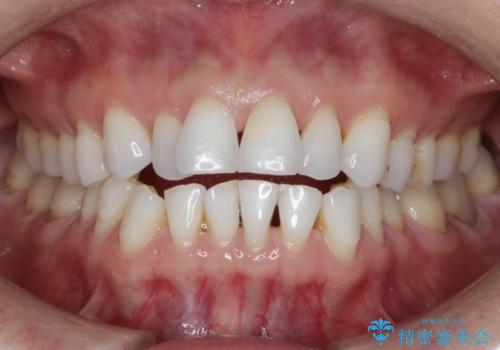

【非抜歯】インビザラインで正しい噛み合わせを

【非抜歯】インビザラインでガタつきと口元を改善!非抜歯でも印象が変わる矯正治療